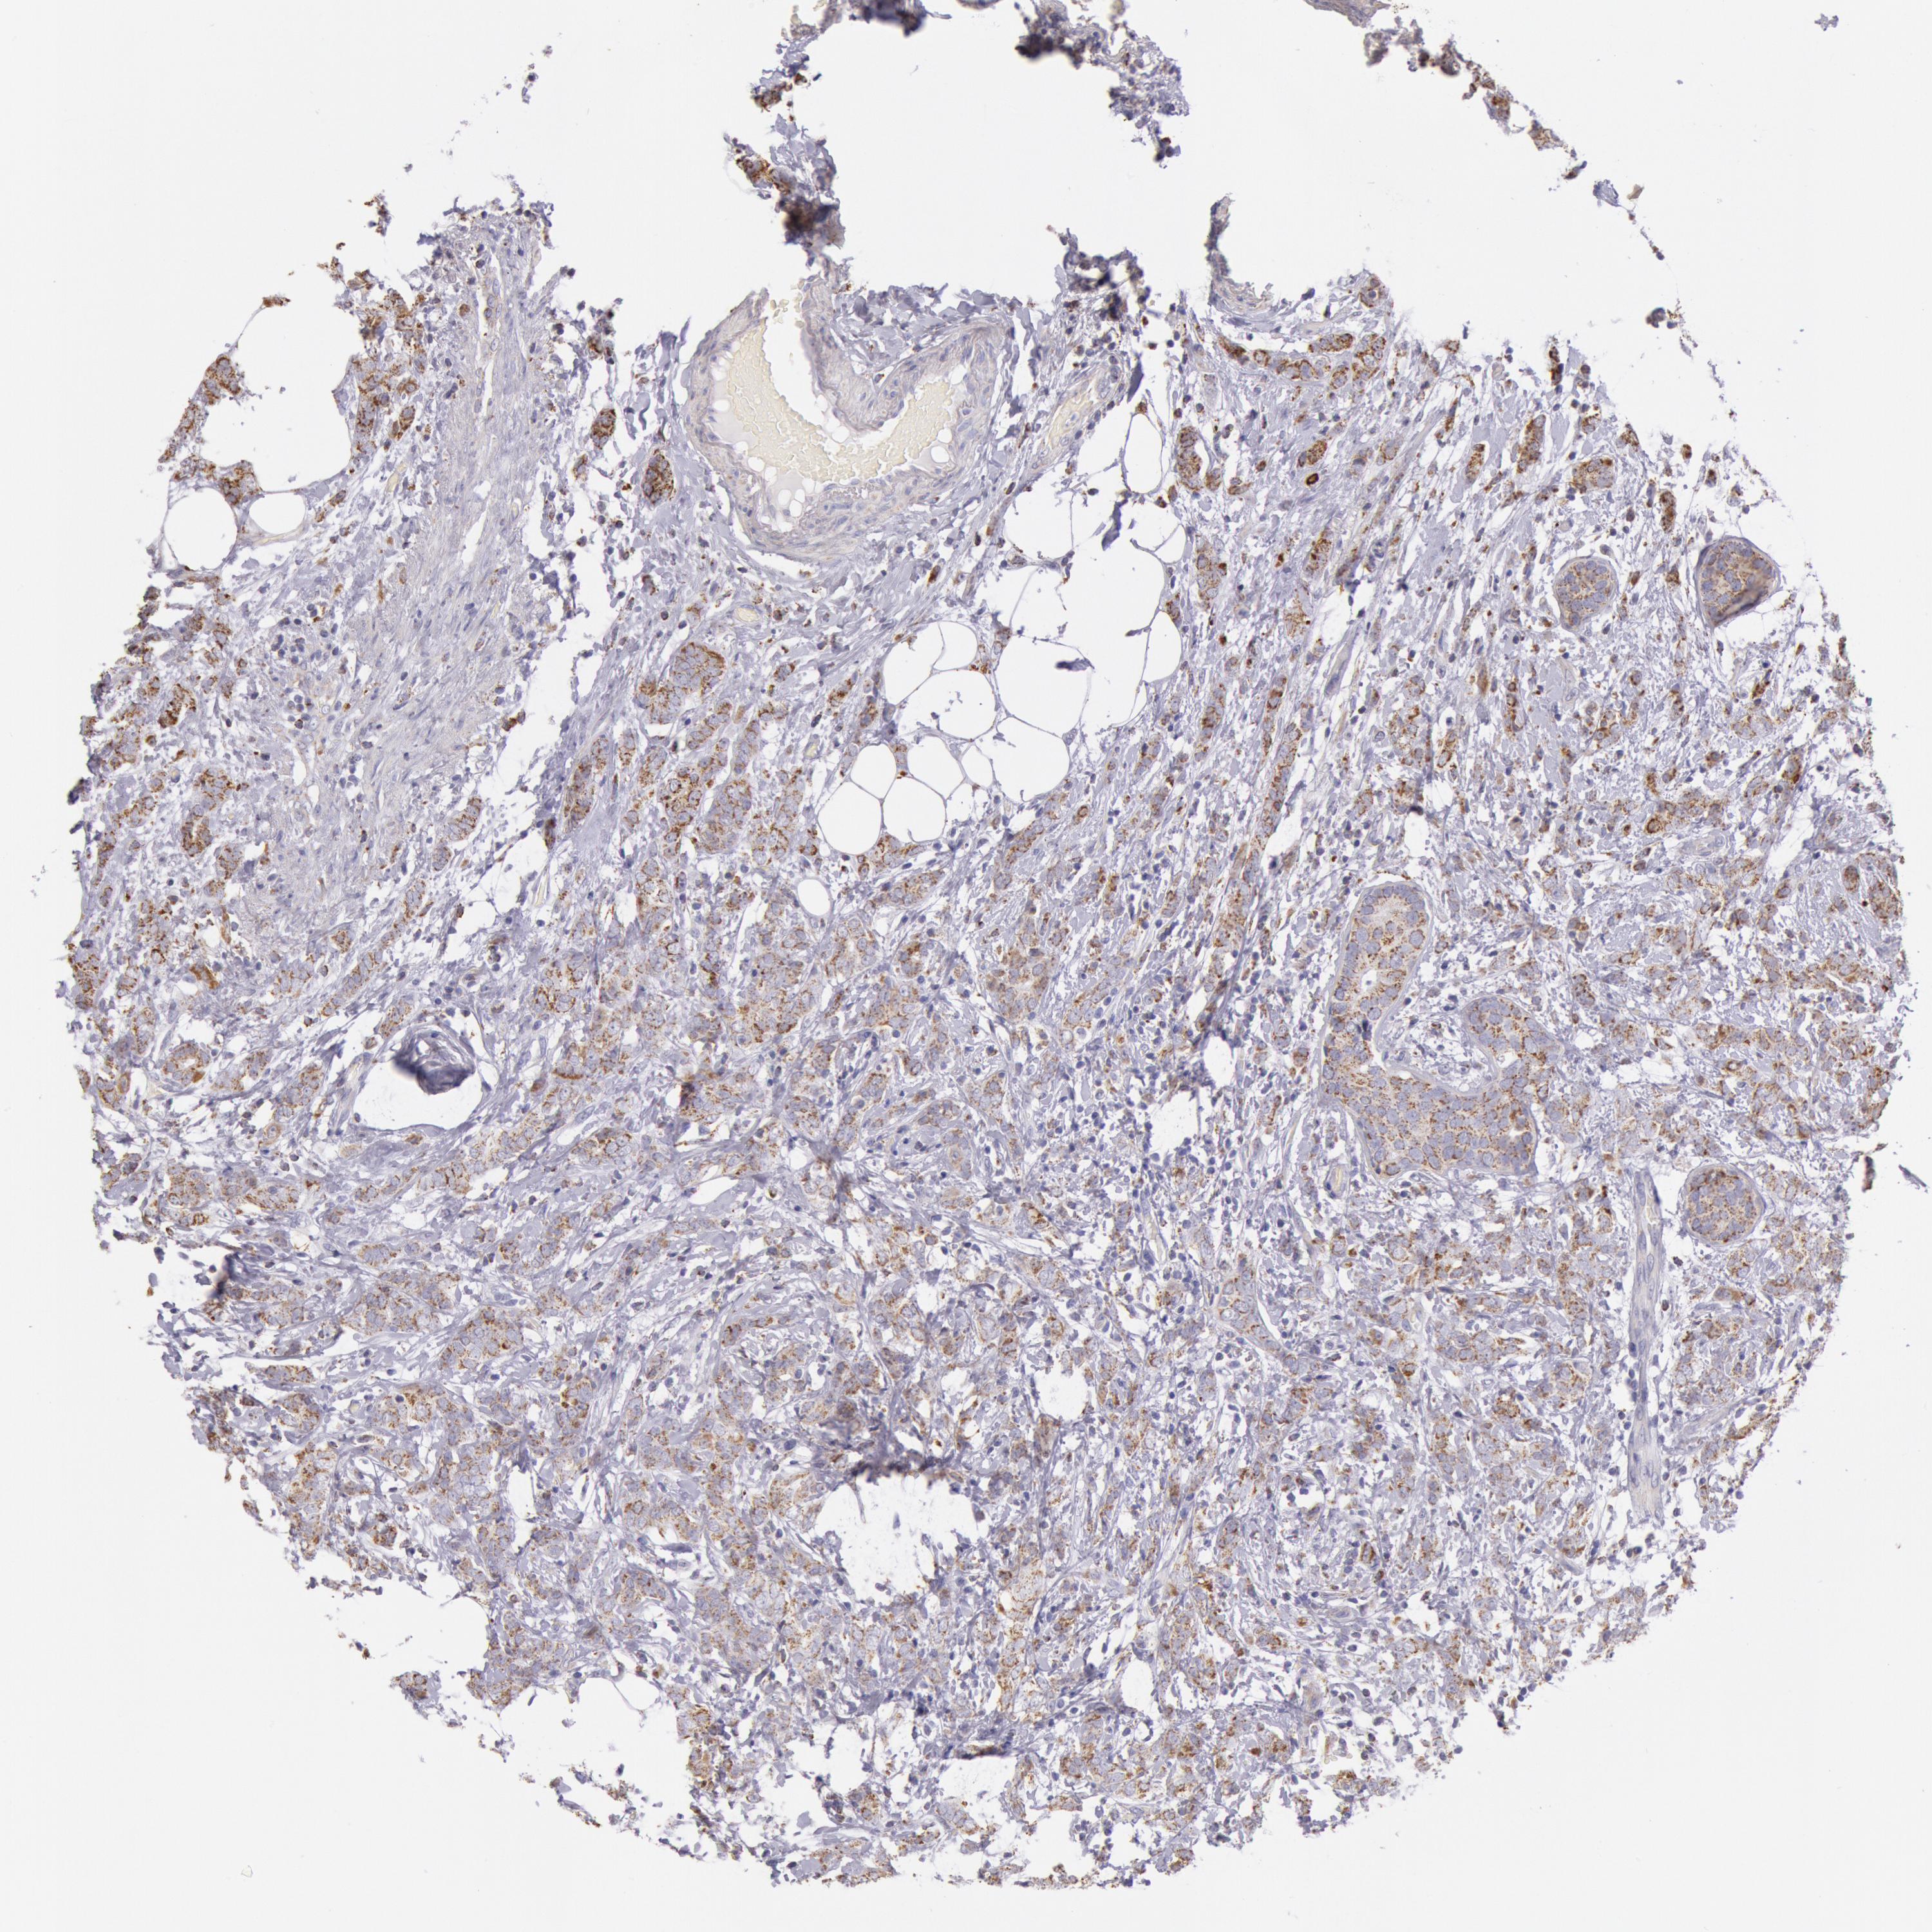

CANCER BREAST CANCER Show tissue menu

BRCA TCGA BRCA VALIDATION PROTEIN EXPRESSION